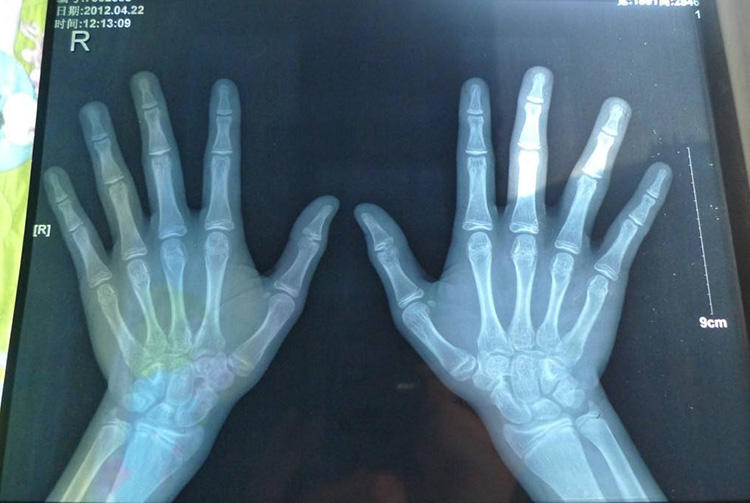

我们都知道的,孩子的成长是有时间限制的,所以骨龄检测,找出原因,及时纠正,切勿影响孩子一生。进行骨龄检测,还能够做到的一件单凭医生观察而做不到的事情,那就是对于孩子骨龄闭合时间的检测。

这项结果的出现,能够为我们提供一个数据,那就是孩子会在什么时候停止生长,孩子在未来还能够长多少。在有了确切的数据之后,进行人工干预指导,孩子才能有长高的可能。